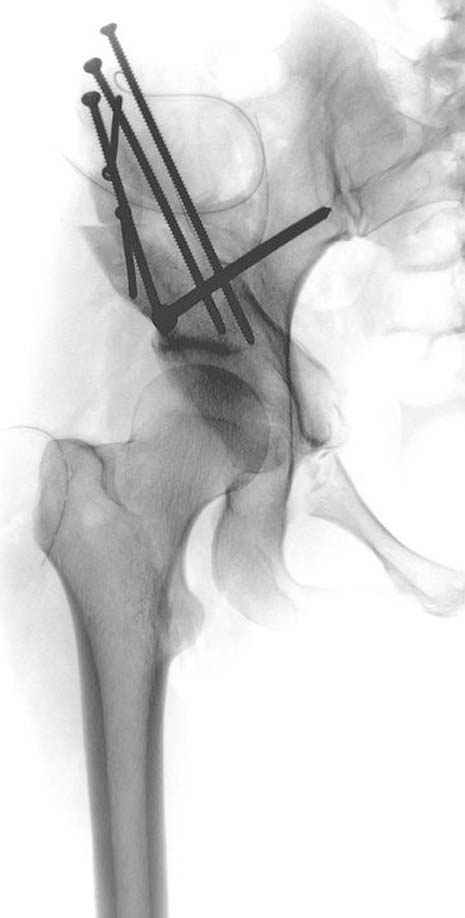

Рис.1 Трехмерная модель тазобедренного сустава с аналогом связки головки бедра. Заметно, что из торца головки выходит капроновый шнур, который с одной стороны прикрепляется к ножке бедренной части модели, а другой его конец, проходя через головку и прикрепляется к вертлужной части модели. Динамометр оказывается не нагруженным, так как аналог связки головки бедра замыкает подвижный узел модели во фронтальной плоскости.

Рис.2 Та же трехмерная модель тазобедренного сустава без аналога связки головки бедра. Пружина динамометра удерживает тазовую часть модели от опрокидывания, поддерживая стабильность так же, как отводящие мышцы обеспечивают ее в отсутствии связки головки бедра.